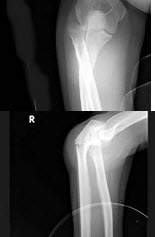

261、单项选择题

男,11岁,左肘外伤,根据所示图像,最可能的诊断是()

A.左肱骨内上髁骨骺Ⅰ度分离

B.左肱骨内上髁骨骺Ⅱ度分离

C.左肱骨内上髁骨骺Ⅲ度分离

D.左肱骨内上髁骨骺Ⅳ度分离

E.左肱骨内上髁骨骺Ⅴ度分离